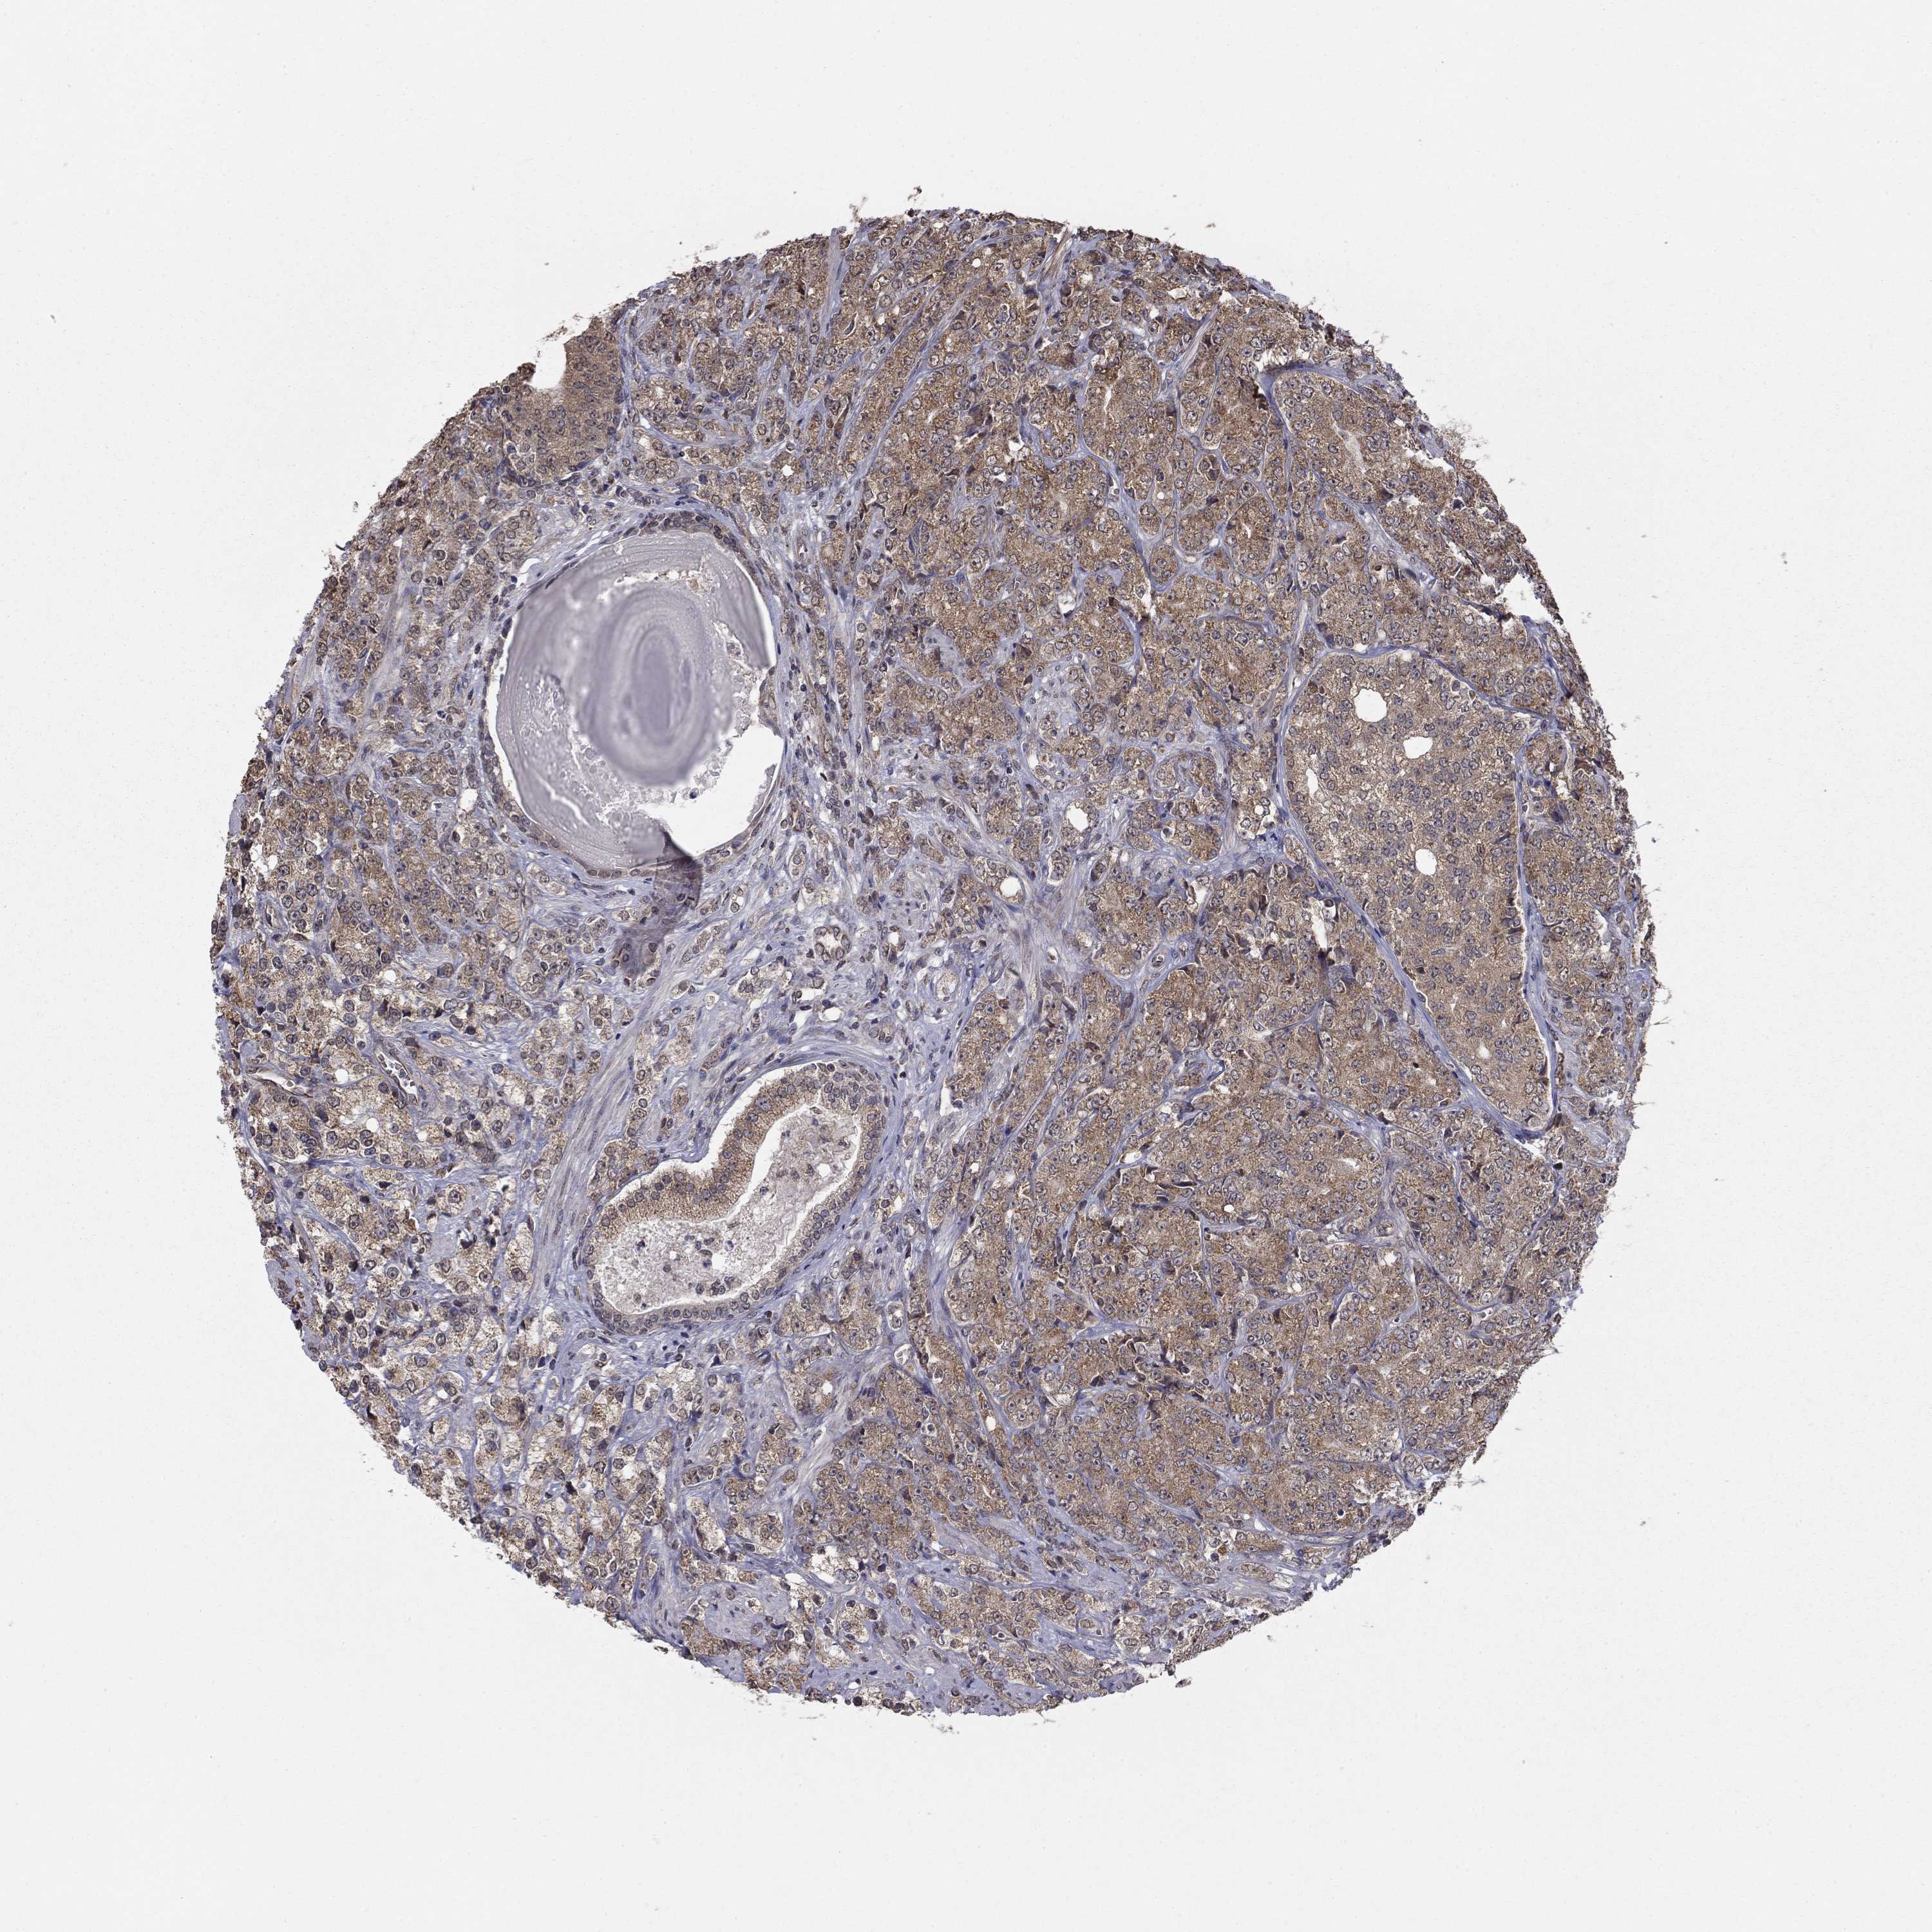

PROSTATE CANCER - Protein expressioni

A mouse-over function shows sample information and annotation data. Click on an image to view it in a full screen mode. Samples can be filtered based on level of antibody staining by selecting one or several of the following categories: high, medium, low and not detected. The assay and annotation is described here.

Note that samples used for immunohistochemistry by the Human Protein Atlas do not correspond to samples in the TCGA dataset.

Antibody stainingi

Antibody staining in the annotated cell types in the current human tissue is reported as not detected, low, medium, or high, based on conventional immunohistochemistry profiling in selected tissues. This score is based on the combination of the staining intensity and fraction of stained cells.

Each image is clickable and will lead to virtual microscopy that enables deeper exploration of all samples and also displays staining intensity scores, fraction scores and subcellular localization as well as patient and tissue information for each sample.

Antibody HPA006584

Antibody HPA061679

Staining

High

Medium

Low

Not detected

Intensity

Strong

Moderate

Weak

Negative

Quantity

>75%

75%-25%

<25%

None

Location

Nuclear

Cytoplasmic/membranous

Cytoplasmic/membranous,nuclear

Adenocarcinoma, Low grade

Adenocarcinoma, High grade

Adenocarcinoma, NOS